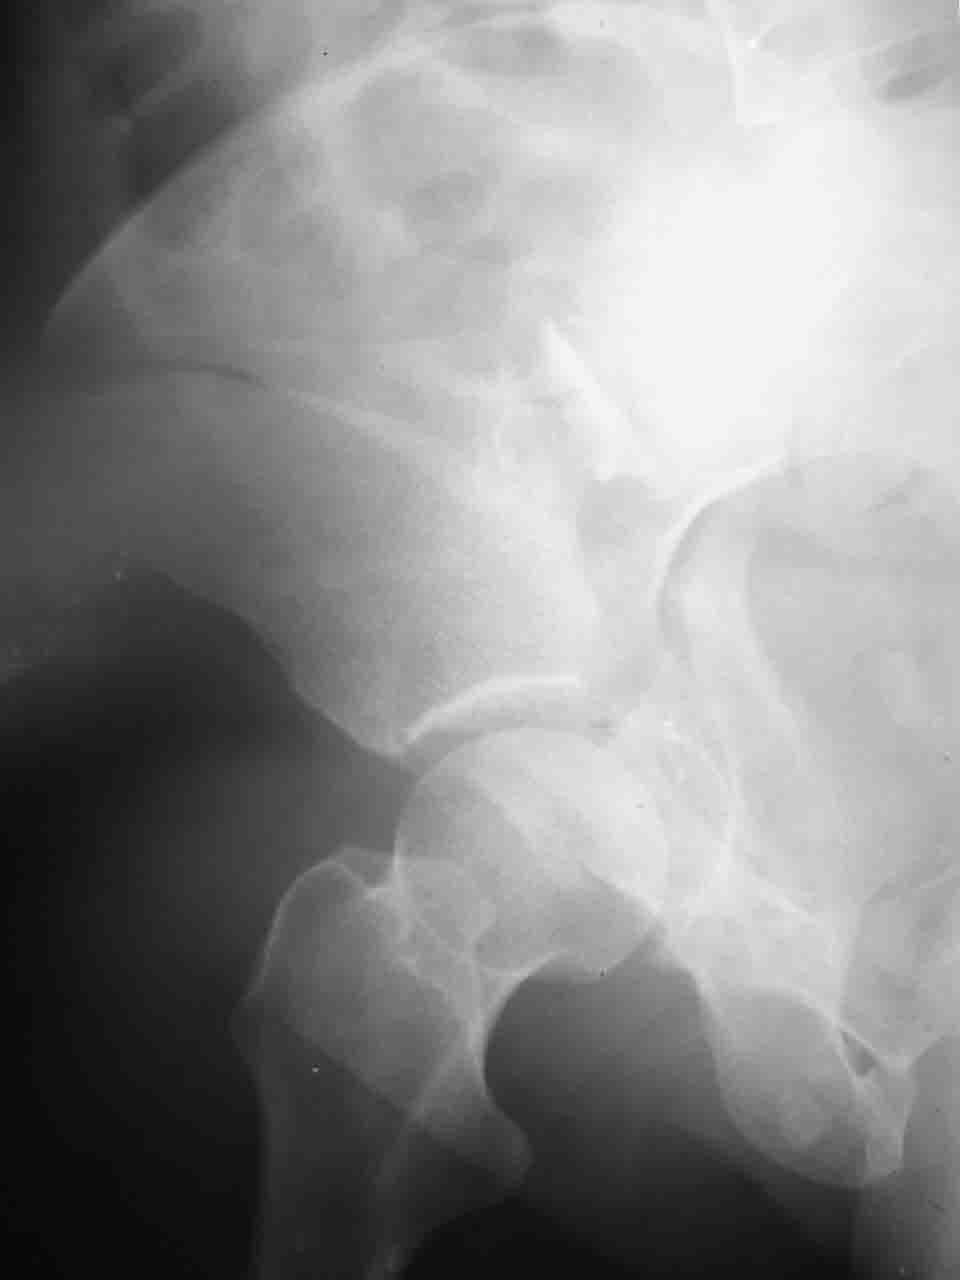

Уважаемые коллеги,43 летний мужчина, попав в автоаварию 13.10.2004, получил оскольчатый перелом обеих колонн левой вертлужной впадины.

На рентгенограммах - высокий двухколонный перелом вертлужной впадины с нарушением конгруэнтности, имеется обратная клиновидность суставной щели.